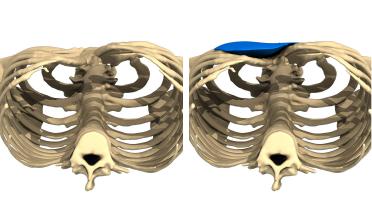

La tecnica di impianto su misura è una tecnica chirurgica minore che consiste nel riempire la concavità creata dal Pectus con un impianto personalizzato. Si tratta di un intervento rapido, a basso rischio, con un risultato immediato e una breve convalescenza.

In questa pagina, troverà i risultati di questa operazione a seconda del tipo di Pectus : mediale, asimmetrico, più o meno profondo o lungo.

Tipo 3 : Asimmetrico,